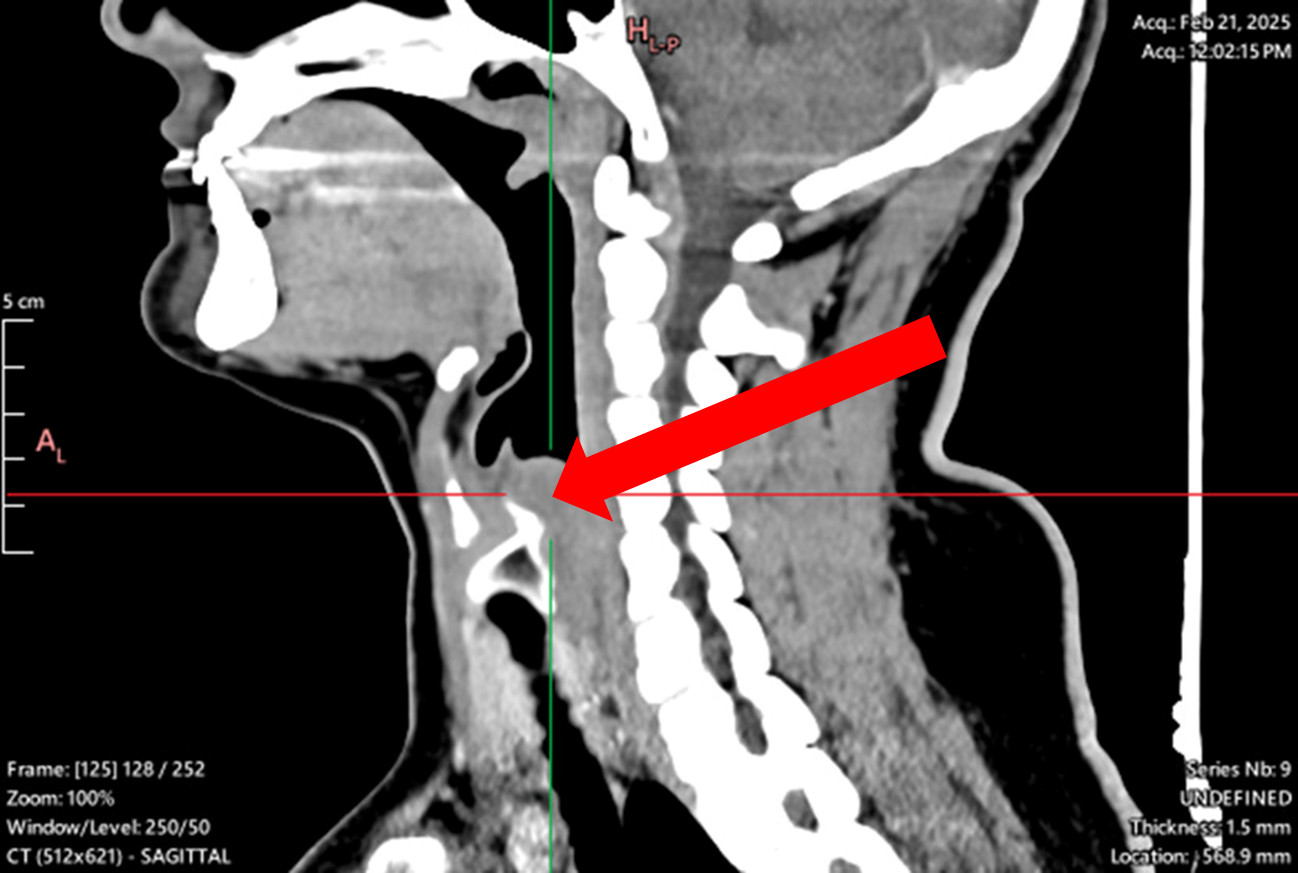

Laryngeal tumor - posterior commissure

Biopsy, granular cell tumor, granular cell myoblastoma, Abrikossoff tumor/div>

Symptoms: hoarseness, sensation of a foreign body in the throat, dysphagia